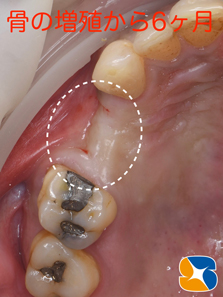

前回の骨の造成手術から6ヶ月後の状態です。とてもふっくらした状態で綺麗に治っています。

2020・3月。

最初の手術開始から9ヶ月後の状態です。本日セラミックの被せ物が完成しました。

1ヶ月前から仮歯を入れて噛むトレーニングを行なっていましたので、違和感もなくスムーズに使用されました。

再生医療を活かして無事にがっちり噛める歯を復活させる事が出来ました。